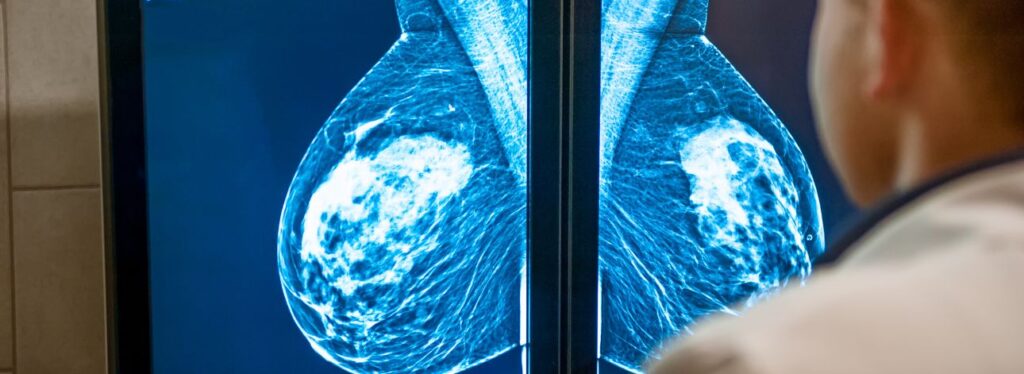

De acordo com a FDA, essa medida pode ajudar a detectar precocemente casos de câncer de mama nos EUA. Pois quase metade das mulheres norte-americanas com mais de 40 anos possuem tecido mamário denso. Segundo a agência, esse tipo de tecido pode dificultar a detecção de cânceres em uma mamografia. Assim como é um fator de risco para o desenvolvimento da doença.

Segundo o CDC (Centros de Controle e Prevenção de Doenças), é complicado diferenciar um tumor do tecido mamário denso, já que ambos aparecem como brancos na mamografia. O comunicado recomenda que as pacientes consultem um médico para descobrir sua densidade mamária e risco de câncer individualmente. A mamografia é um dos exames mais precisos para rastrear e detectar câncer.